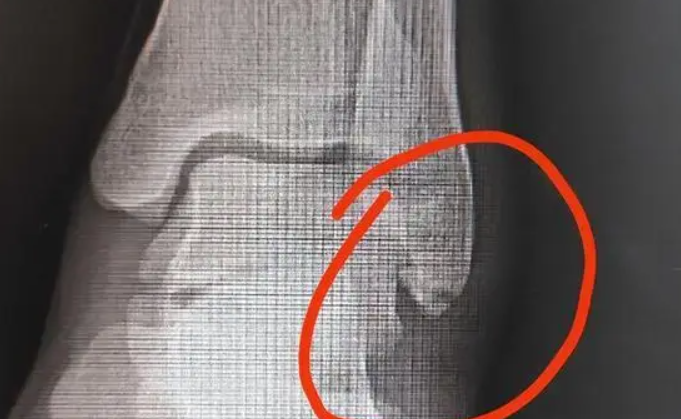

骨裂根据骨折位置的不同,分为纵行骨折、横行骨折、斜行骨折和螺旋骨折等。轻微骨裂通常指的是非移位性骨折或者是完全性、不影响四肢功能的骨折。这种骨裂一般不需要手术治疗,可以到保守治疗方法。